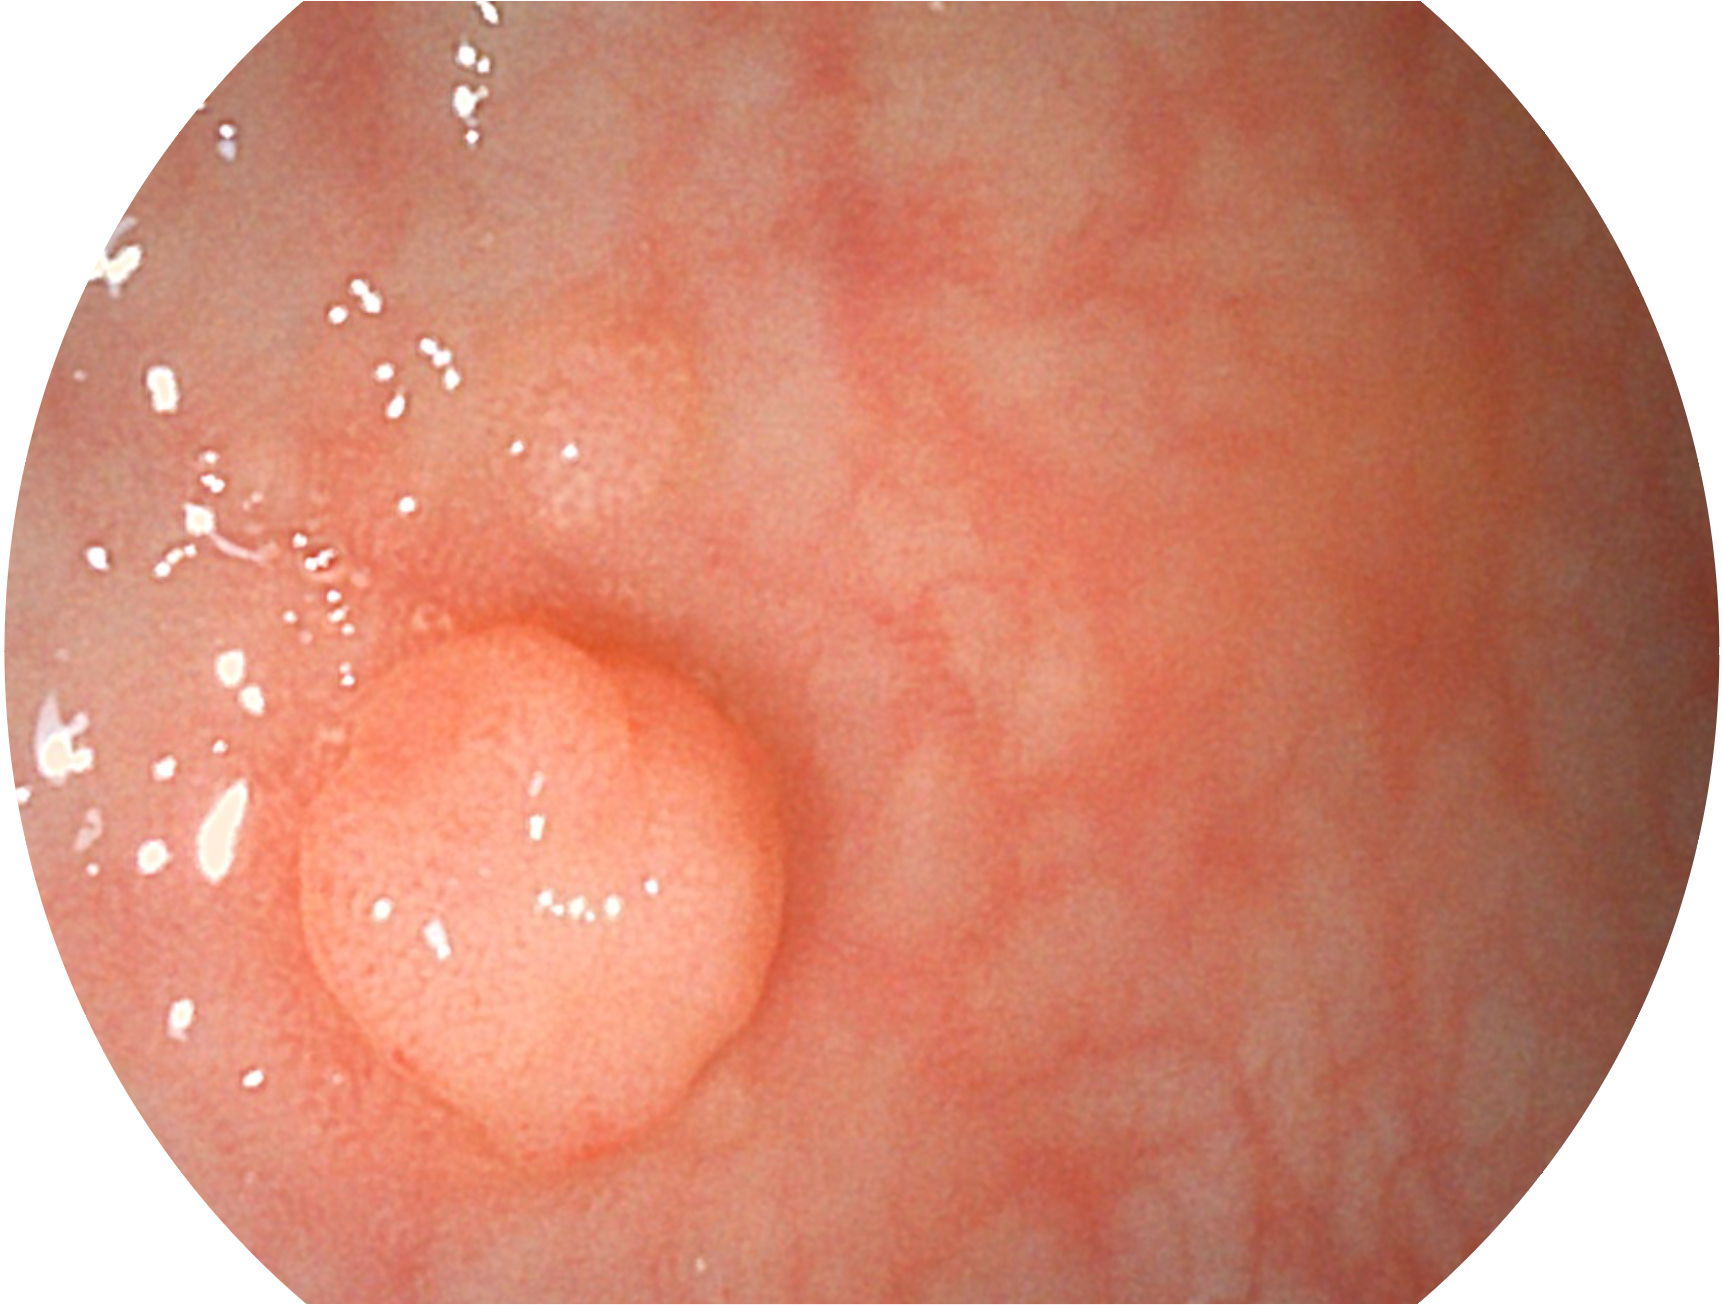

云顶集团官网新开发的内镜染色技术,主要是基于多波长LED 光源的开发,VLS-55Q 四波长LED 光源是由四个不同颜色的LED光按照相应照明模式所规定的特定发光比例进行合束后形成,合束后形成的照明光的光谱由红光、绿光、蓝光及蓝紫光这四个不同的波段范围构成。具有更高光谱自由度,通过光谱比例的控制,实现了聚谱成像技术,英文全称为“Spectral Focused Imaging, SFI”,缩写为“SFI”和光电复合染色成像技术,英文全称为“Versatile Intelligent Staining Technology, VIST”,缩写为“VIST”。